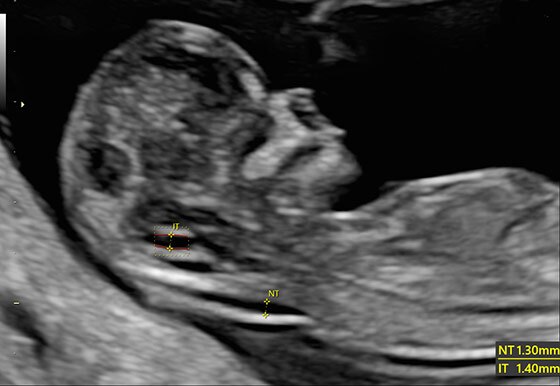

- Автоматический расчет толщины воротникового пространства SonoNT и размера четвертого желудочка SonoIT

- SonoNT (Sonography-based Nuchal Translucency) и SonoIT (Sonography-based Intracranial Translucency) – технологии, позволяющие в полуавтоматическом режиме измерять толщину воротникового пространства и размеры IV желудочка головного мозга плода в I триместре.

- Функции измерения толщины воротникового и внутричерепного пространств SonoNT иSonoIT обеспечивают воспроизводимость результатов и легко интегрируются в исследования, проводимые в первом триместре.